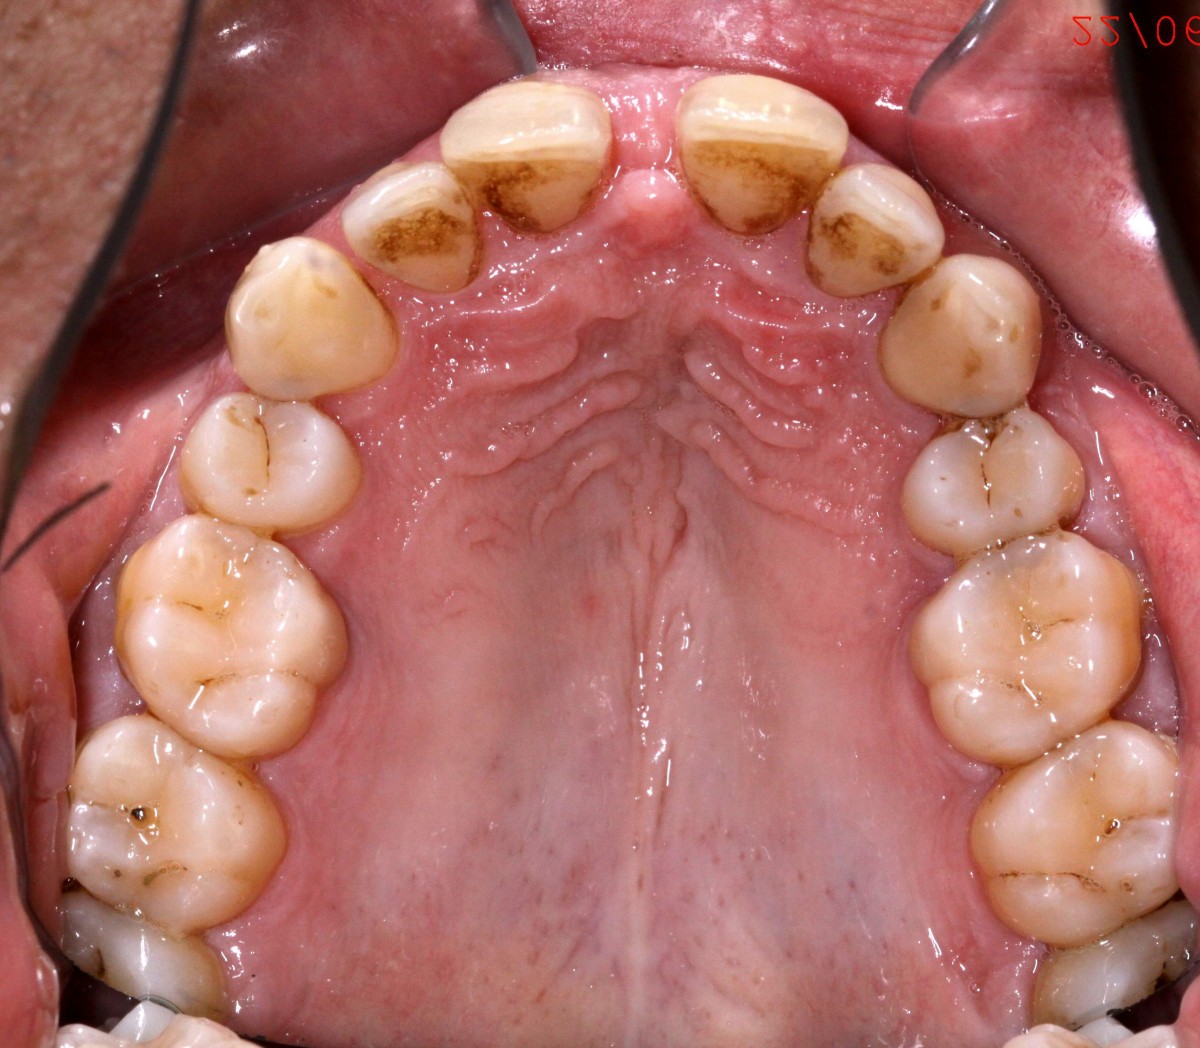

G.L., 51 years old patient, pre- sented to the clinic with Class I malocclusion, deep bite with complete coverage of lower in- cisors, big median diastema between teeth #11 and #21, lack of interdental papilla and poor oral hygiene (figs. 3, 4).

Lower incisors erupted verti- cally and created 2 planes of occlusion and exaggerated curve of spee in the lower arch. The upper lip “pushed” the an- terior incisors lingually and consequently the bite was deepened. Oral hygiene is poor mainly due to the crowding of the lower incisors. The upper diastema resulted in the loss of the interdental papilla between the central incisors (figs. 5, 6).

Patient had gone through pre- vious orthodontic treatment

with extraction of upper first premolars (#14, #24). Space between #11-#21 is slowly opened during the years and space start to develop distally to the upper lateral incisors. Lower incisors are hitting traumatically the palate creat- ing proliferation of the epithe- lium and constant inflamma- tion. Lower anterior crowding is around 4.5 mm (#33-#43) (figs. 7, 8).